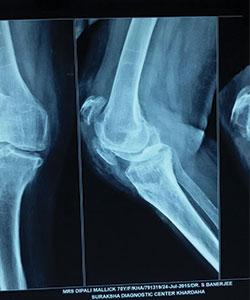

Case 2: Patella Fracture

Patella fracture in a 70years old female.

X-RAY 1

patella fracture (pre operative x-ray)

X-RAY 2

post operative x-ray of patella fracture